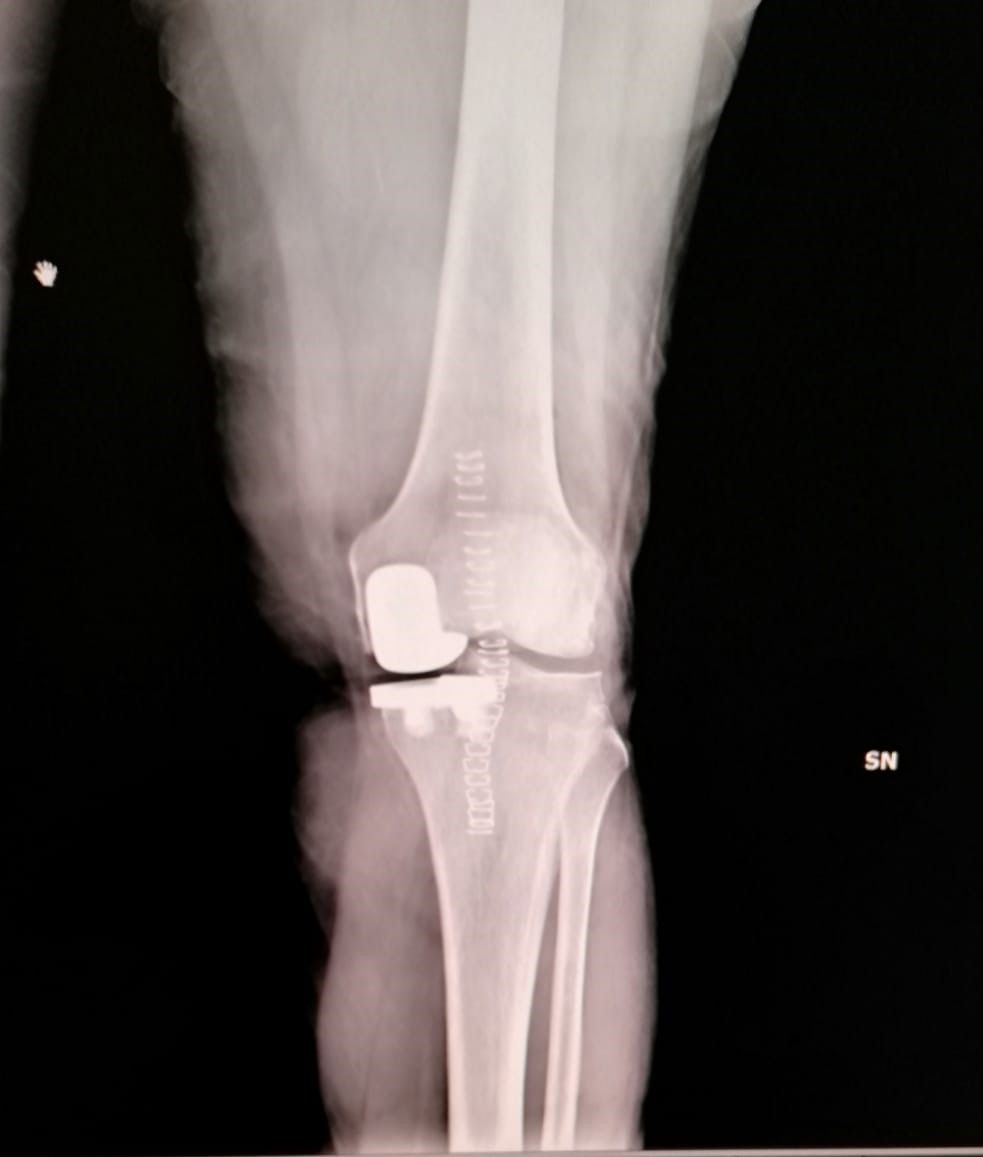

- protesi totale di ginocchio

- protesi mono-compartimentale del ginocchio

Dopo due anni di tentativi vani e aver consultato vari ortopedici, finalmente il dr.Zornetta mi ha illustrato bene la situazione del mio ginocchio. Persona che subito ti trasmette fiducia, competenza e finalmente ti spiega con chiarezza cosa hai, che dire e' una persona semplice e simpatica. Cosi' dopo gli ultimi esami mi ha consigliato l intervento al ginocchio con mezza protesi, mi sono fidata di lui anche perche' mi avrebbe operata lui stesso. A me e' andata tutto bene e lo ringrazio!

Medico competente e preparato, presente durante il ricovero e successivamente, nel mio caso protesi ginocchio. Disponibile e gentile. Esperienza positiva.

Il dottor Zornetta mi ha spiegato molto chiaramente tutti i punti che hanno portato alle operazioni per le protesi a entrambe le ginocchia. Presente anche nel post operazione. Sono molto contenta dei risultati e consiglio vivamente questo dottore.

Ottimo ortopedico,ti segue sino alla fine della operazione e oltre.quando hai bisogno,c'è.ho fatto 2 protesi ai ginocchi da lui.